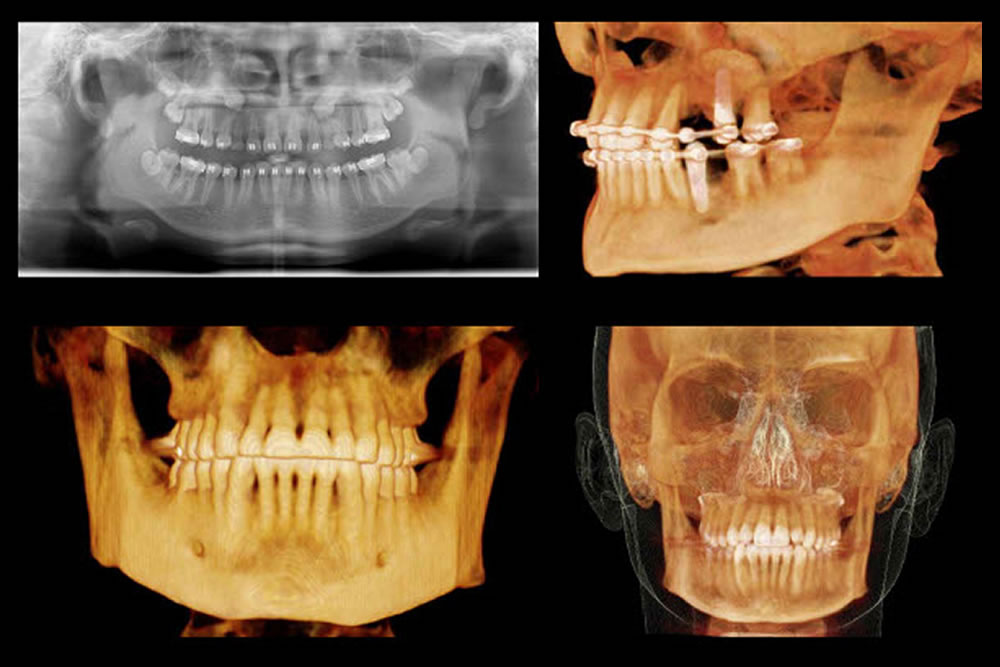

精密検査(CT撮影・レントゲン・模型)

インプラントは骨に人工歯根を埋め込む治療なので、顎の骨の量や位置、神経・血管の位置を正確に把握する必要があります。

- 歯科用CT撮影:立体的に骨の状態を把握

- レントゲン・口腔内写真:全体の確認

- 噛み合わせチェック・歯型採取